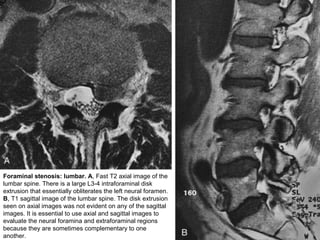

Foraminal stenosis: lumbar. A, Fast T2 axial image of the

lumbar spine. There is a large L3-4 intraforaminal disk

extrusion that essentially obliterates the left neural foramen.

B, T1 sagittal image of the lumbar spine. The disk extrusion

seen on axial images was not evident on any of the sagittal

images. It is essential to use axial and sagittal images to

evaluate the neural foramina and extraforaminal regions

because they are sometimes complementary to one

another.